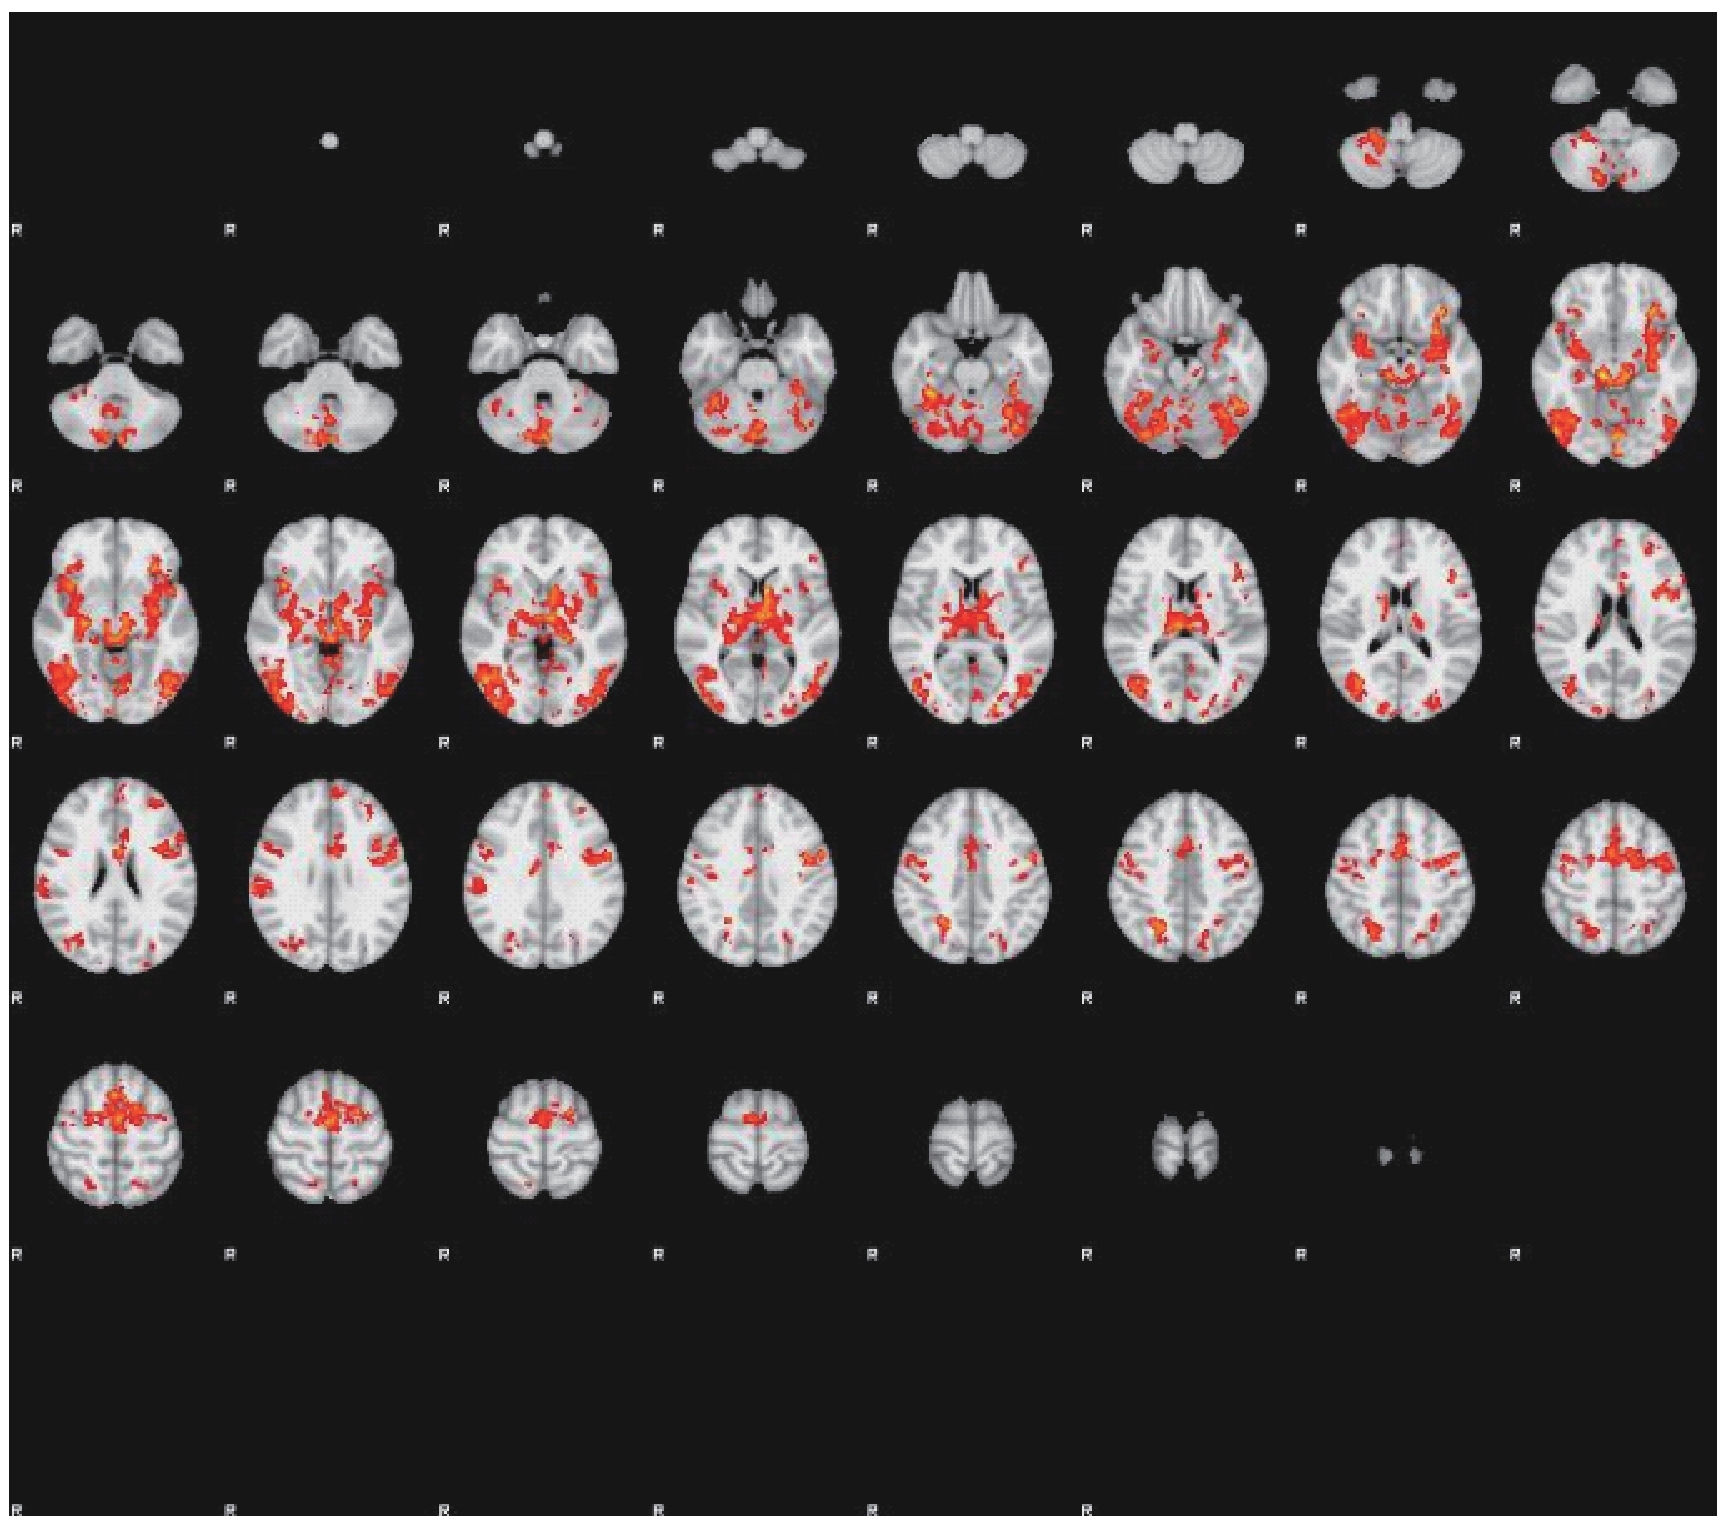

| Active brain region | Cluster extreme point (MNI coordinate) | Cluster extremum( Z-max) | P value | ||

|---|---|---|---|---|---|

| X | Y | Z | |||

| Left anterior cingulate cortex | -6 | 12 | 42 | 4.71 | <0.001 |

| Right amygdala | 22 | -4 | -16 | 4.75 | <0.001 |

| Left amygdala | -20 | -6 | -18 | 4.74 | <0.001 |

| Left insula, temporal pole | -44 | 12 | -8 | 4.61 | <0.001 |

| Left orbital frontal cortex, temporal pole | -30 | 12 | -20 | 4.64 | <0.001 |

| Right insula, orbital frontal cortex | 40 | 16 | -8 | 4.68 | <0.001 |

| Right thalamus | 4 | -18 | 0 | 4.79 | <0.001 |

| Left thalamus | -10 | -22 | -2 | 4.81 | <0.001 |

| Left temporal pole, orbital frontal cortex, parahippocampal gyrus | -30 | 8 | -22 | 4.68 | <0.001 |

| Right hippocampus, parahippocampal gyrus | 24 | -22 | -16 | 4.02 | <0.001 |

Tab 1 Active brain regions in TMD patients with temporomandibular joint pain under anxiety